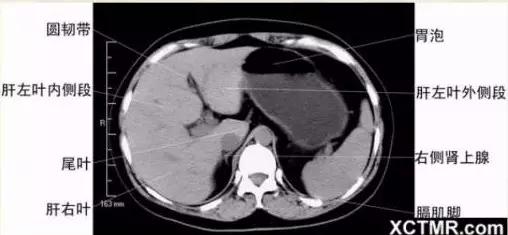

腹部CT